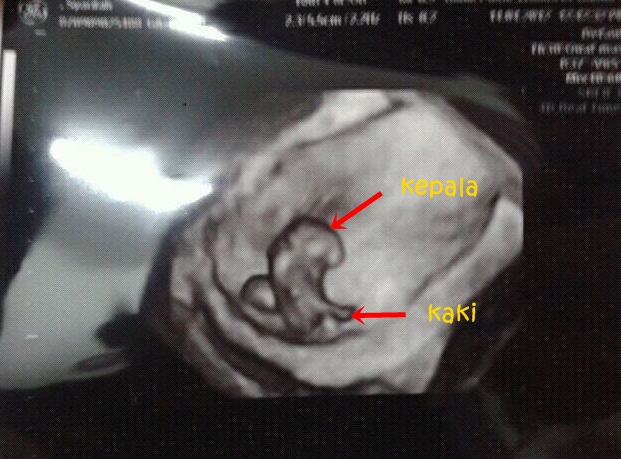

Lepas tu barulah Doktor suruh berbaring di atas katil untuk scan. Mula2 tu NurNiz malu sangat nak tunjukkan perut masa scan, tapi takpalah sebab Doktor tutup lampu jadi keadaan dalam bilik tu agak gelap. Mula2 Doktor tunjukkan kantung baby kat NurNiz. Kalau ada kantung ni maksudnya konpemlah anda sedang mengandung. Kemudian Doktor zoom plak ke dalam kantung & ternampaklah baby NurNiz. Kecil ja masa tu ukurannya hanya 1.81cm (besar pemadam pensel ja) tapi masa tu dah nampak akan bentuk kepala & kaki baby. Kemudian Doktor tunjukkan plak dengupan jantung & siap pasang mikrofon lagi untuk dengar dengupan jantung baby. Alahai kecil2 pun dah ada jantung yang berdengup. Dengupan jantung baby kuat & laju sangat dalam 180 dengupan per minit tapi Doktor kata normal bagi baby dalam kandungan. Macam tak percaya plak masa tu NurNiz dah nak jadi seorang Mommy :).

| 8 minggu scan. My baby :) |